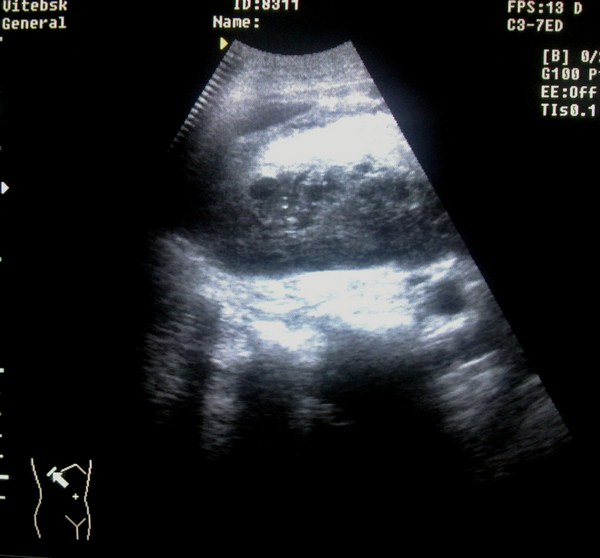

Мужчина,43года из пульмонологического отделения (в плановом порядке), жалобы на боли в области грудной клетки справа. Анамнез: травма в быту, упал с лестницы, ударился правой стороной (5-е сутки)

ОАК: Er 2.8 Hb 98 ц.п 0.88 Т 36,8 В анамнезе 2 года назад оперирован по поводу рака гортани.

ДЗ: Постравматическая н/долевая правосторонняя пневмония. З/перелом X-XI ребер справа. Анемия неясной этиологии.

Первым делом необходимо определиться с анатомической локализацией образований.

Снимки 2-3 - не в брюшной ли полости жидкость?

По-любому далее я бы сделал диагностическую пункцию с лаб исследованием пунктата. Далее - по ситуации.

Травма+анемия+ЭТО =?

Если маркеры стоят правильно, то это поддиафрагмальная внутрибрюшная гематома.

Возможно и внутрибрюшная, а может и подкапсульная гематома. Кстати, каковы критерии диф.диагноза?